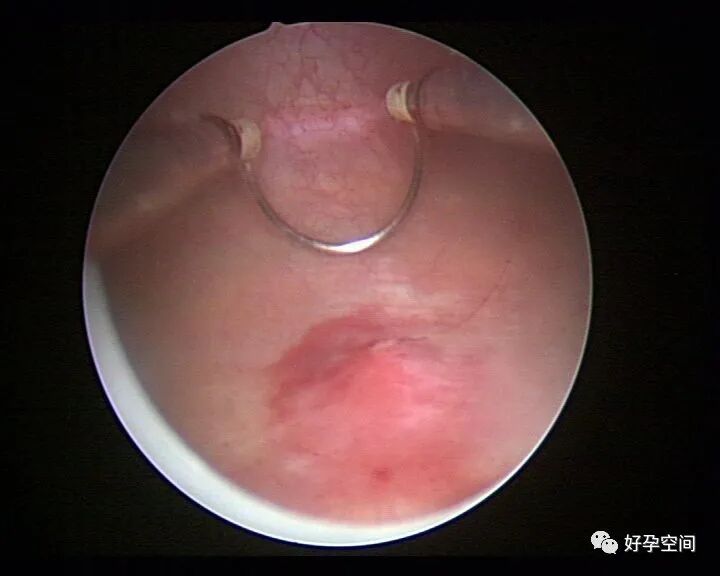

病例3:(病人年龄及取卵个数不详)取卵术后血尿膀胱内血块尿潴留,膀胱灌洗效果不佳,宫腔镜探查膀胱,清除血块,膀胱多处穿刺伤,电凝止血。

病例4:32岁,取卵13枚,取卵术后血尿膀胱内血块尿潴留,膀胱灌洗效果不佳,宫腔镜探查膀胱,清除血块,膀胱底见穿刺伤,电凝止血。